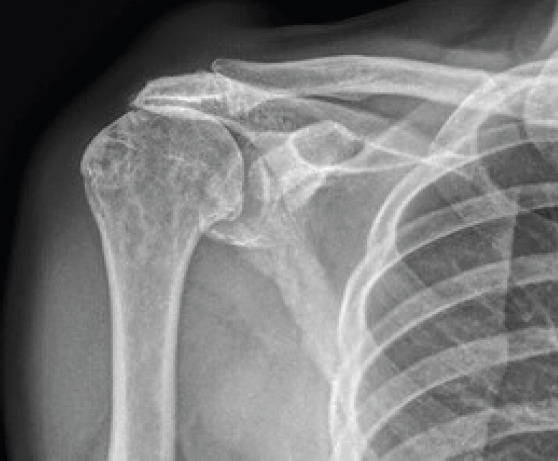

Case report: We present to you a 77-year-old male patient with hypertension and diabetes, who came with a painless swelling over the right shoulder, gradually increasing in size for the first 6 months. He gave a prior history of pain in the shoulder associated with stiffness, depicting a frozen shoulder 5 years ago. On examination, the swelling was soft, cystic, non-reducible, fluctuant, measuring 3 × 3 cm centred over the AC joint. The range of motion was near normal, comparable to the opposite side, associated with crepitus, although pain free. Clinical special tests revealed intact but weak cuff muscles. Imaging was performed that revealed superior migration of the humeral head and near complete chronic supraspinatus tear with glenohumeral arthritis on radiograph. Magnetic resonance imaging showed synovial thickening with a cystic homogenous swelling above the AC joint, a cutoff geyser sign with no communication to the AC joint or subacromial bursa. Complete excision of the cyst in toto was performed with no additional procedure. The histopathological examination revealed a ganglion cyst.